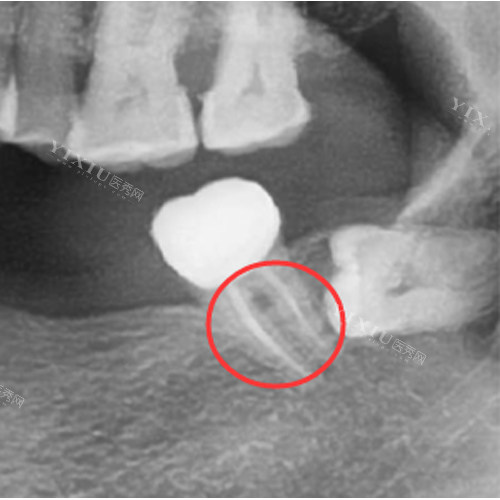

根管治疗后的牙齿